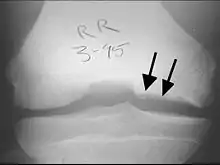

X-rays show lucency of the ossification on the anterior aspect of the knee in juvenile patients. In older people, the lesion typically appears as an area of osteosclerotic bone with a radiolucent line between the osteochondral defect and the epiphysis. The visibility of the lesion depends on its location and on the amount of knee flexion used. Harding described the lateral X-ray as a method to identify the site of an OCD lesion.[36]